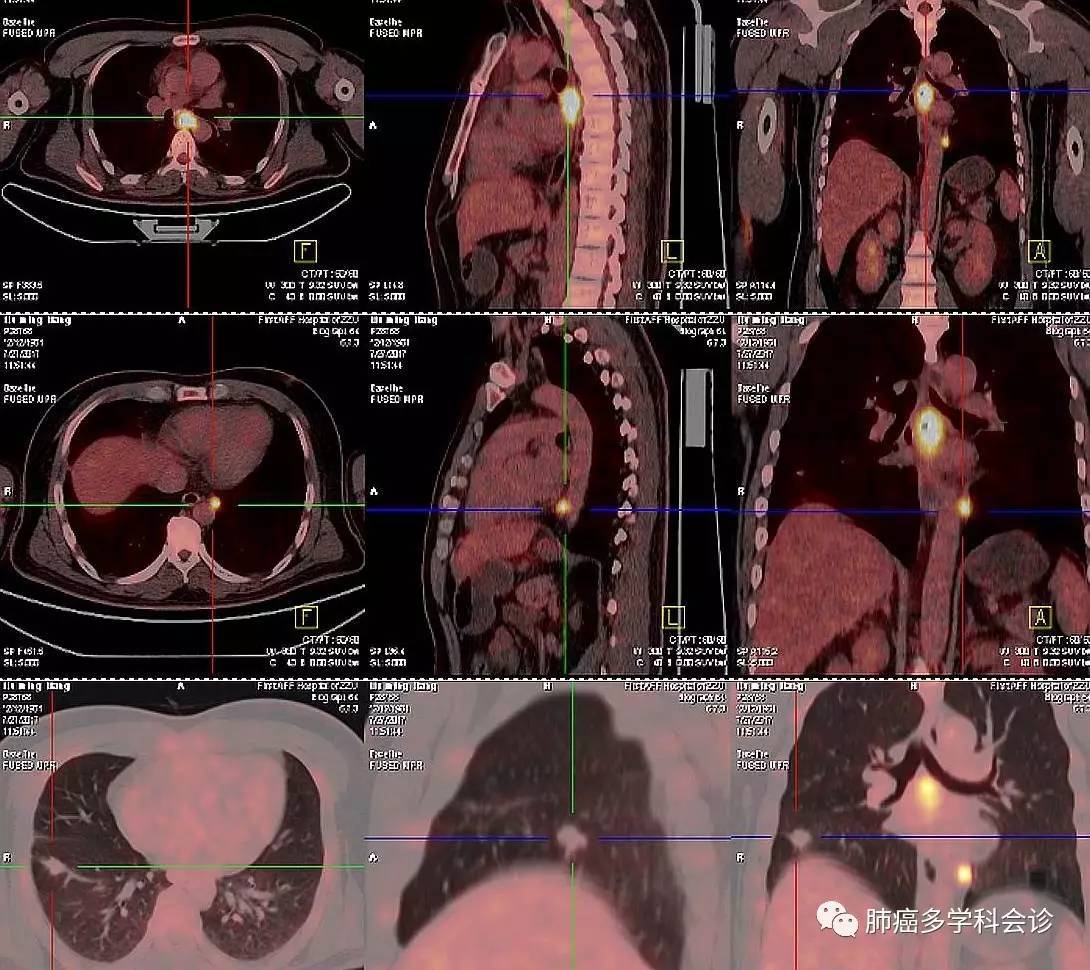

本周四下午,向与会的会诊专家们展示了一位年轻男性患者的 PET-CT 图像(2017-07-27),下图集中了患者体内的所有被发现的肿瘤病变。

部分参加专家认为是食管癌肺转移,也有人认为同时患有食管癌和肺癌。

其实是晚期肺癌,治疗 1 年后发现食管转移!